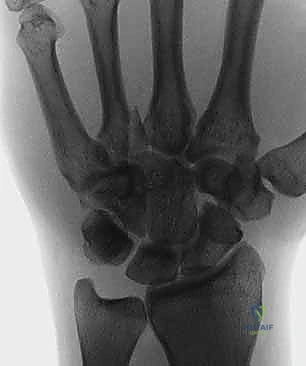

يتكون الرسغ من ثماني عظام صغيرة تُعرف بعظام الرسغ (Carpal bones)، مرتبة في صفين (صف قريب وصف بعيد). بينما يستحوذ العظم الزورقي (Scaphoid) على النصيب الأكبر من الكسور والاهتمام الطبي، فإن العظام السبعة الأخرى تلعب أدواراً حاسمة لا تقل أهمية.

التشخيص هو المرحلة الأهم. الأشعة السينية العادية (X-rays) قد لا تظهر هذه الكسور الدقيقة في البداية بسبب تراكب عظام الرسغ. هنا تبرز خبرة الأستاذ الدكتور محمد هطيف في صنعاء، حيث يعتمد على بروتوكولات تشخيصية عالمية.

- الأشعة السينية بوضعيات خاصة: أخذ صور بأكثر من زاوية لفك تراكب العظام.

- الأشعة المقطعية (CT Scan): المعيار الذهبي لتشخيص كسور عظام الرسغ المخفية وتحديد حجم التفتت والتزحزح.

عظام الرسغ صغيرة جداً ومتراكبة فوق بعضها البعض. في الأشعة السينية العادية (2D)، قد تخفي عظمة ظلاً لعظمة أخرى، مما يجعل الشروخ الدقيقة غير مرئية. لذلك يعتمد الدكتور هطيف على الفحص السريري الدقيق والأشعة المقطعية (CT).